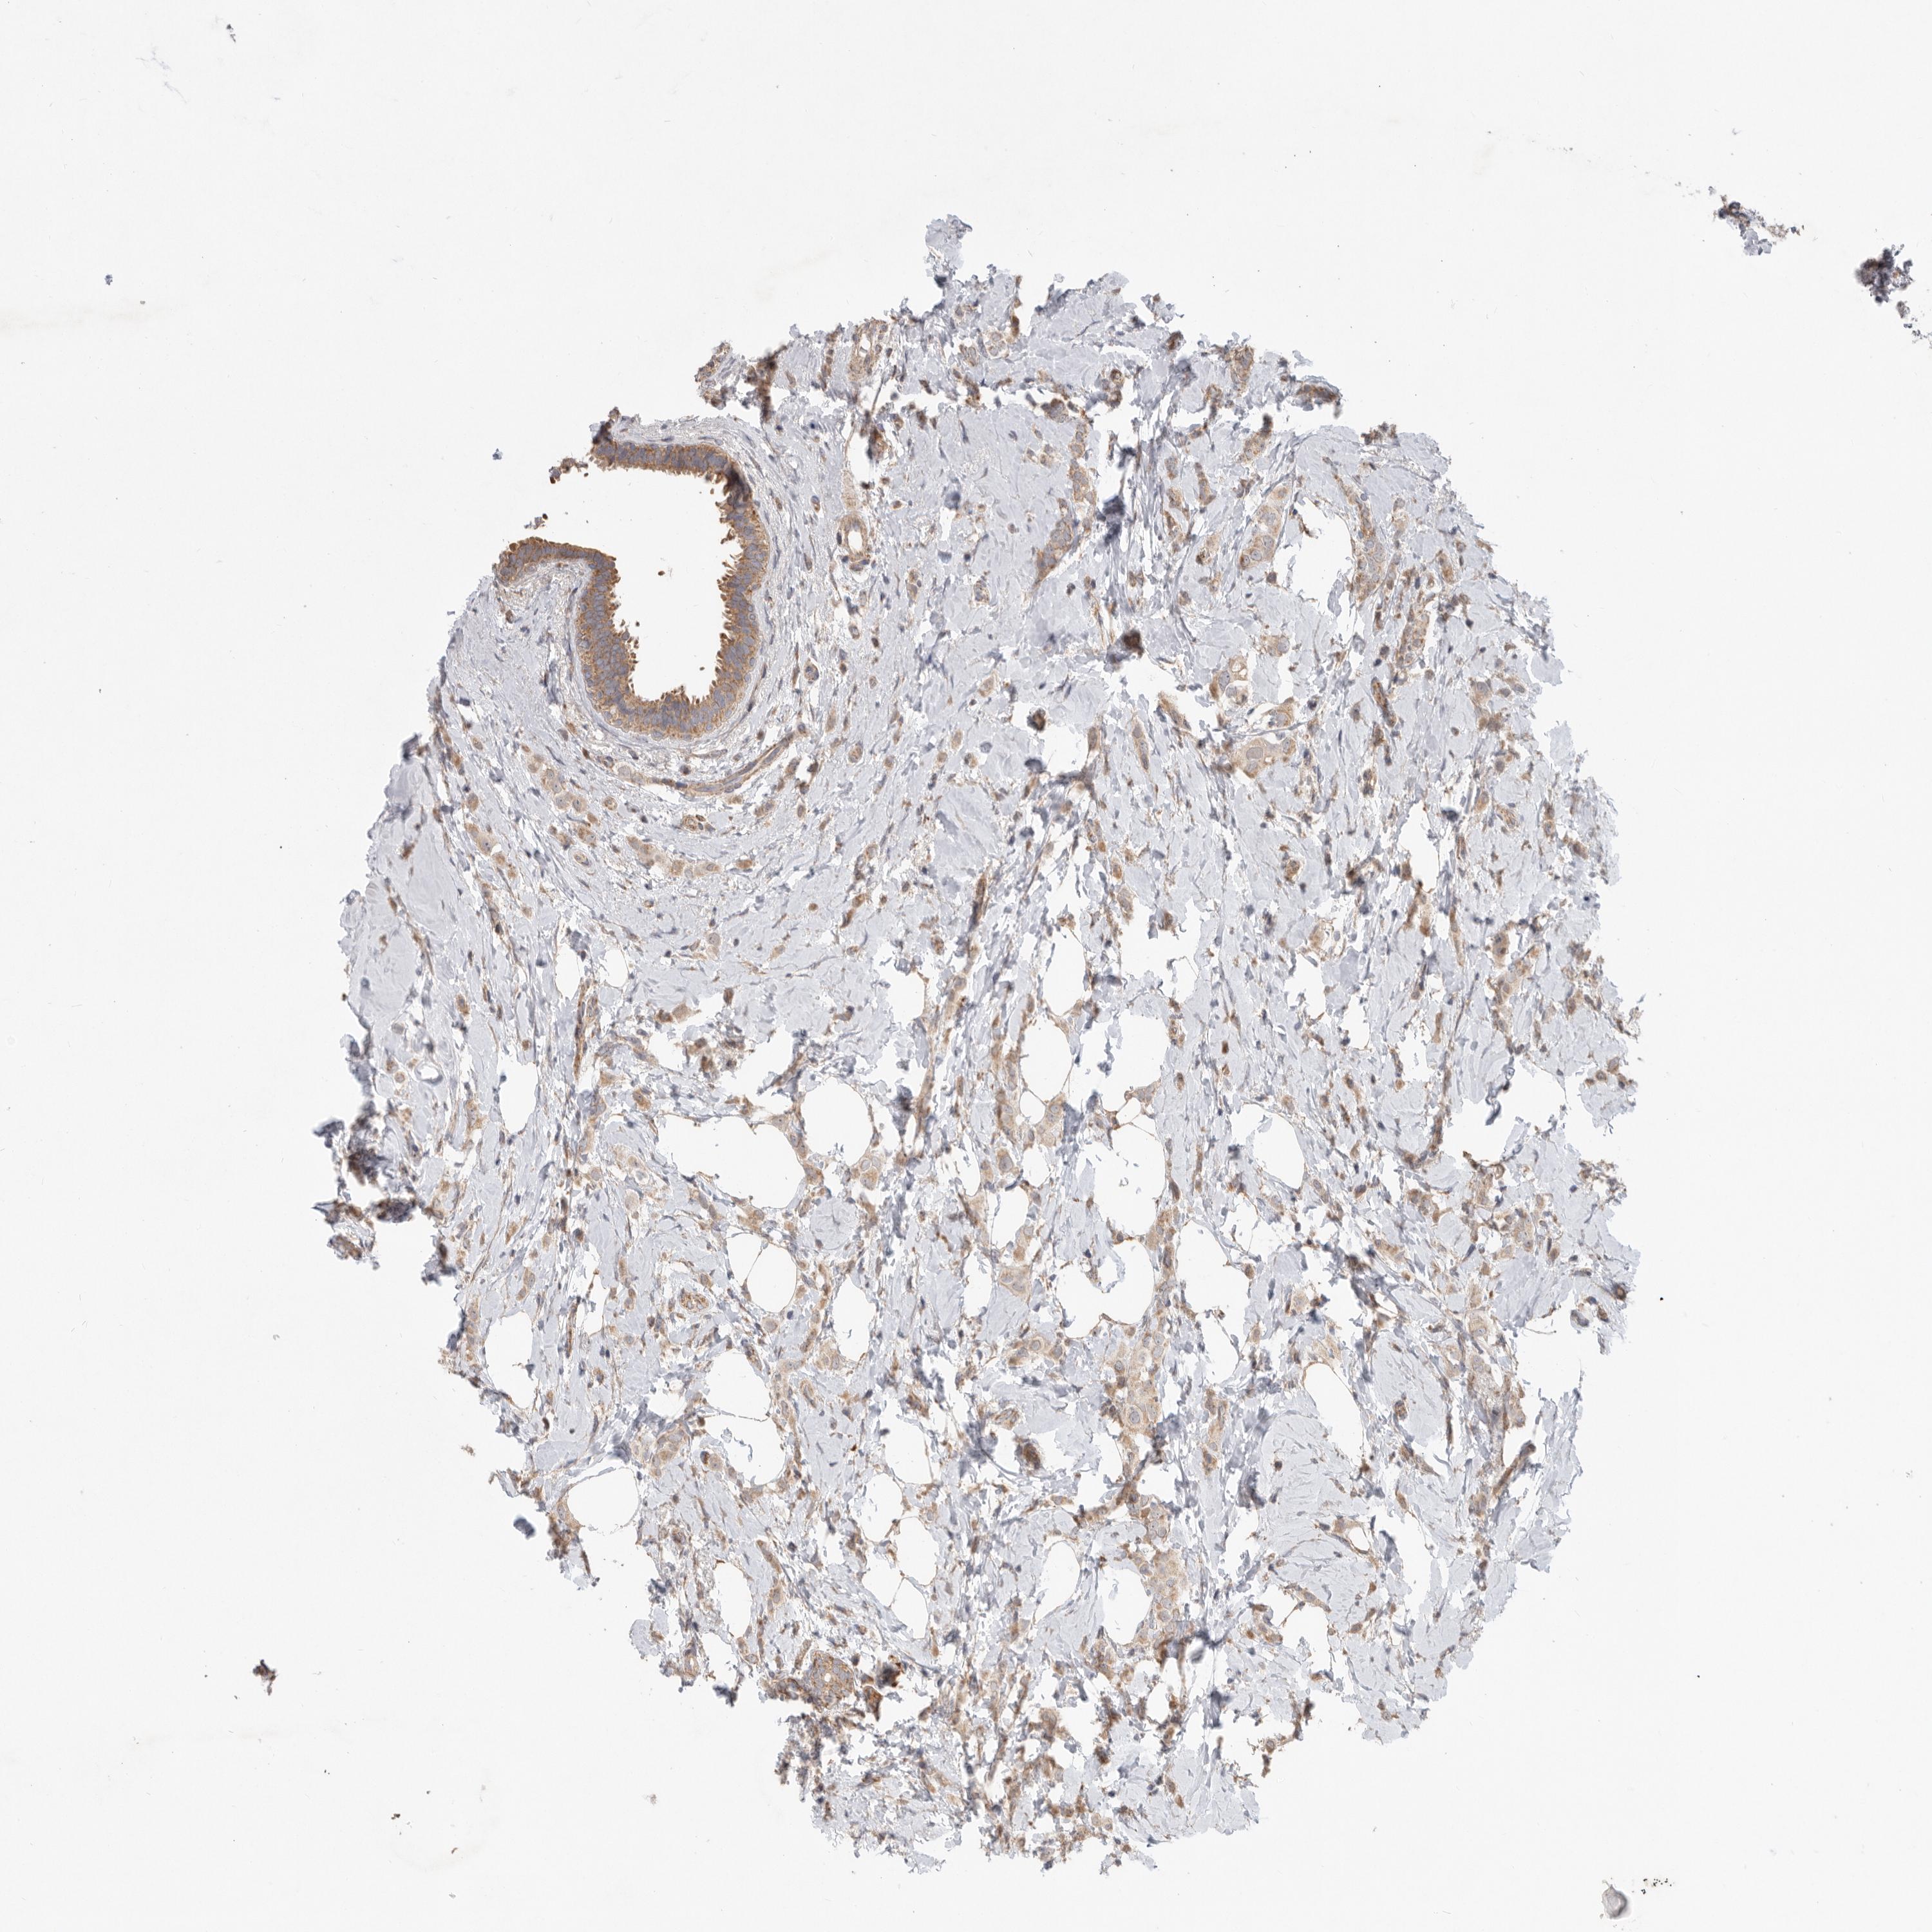

BRCA TCGA BRCA VALIDATION PROTEIN EXPRESSION

Breast cancer

Human cancer